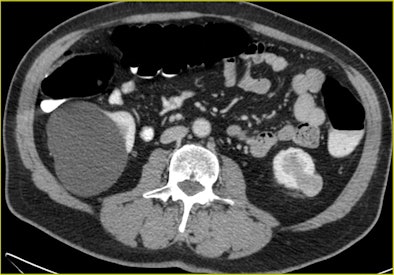

| A 70-year-old man underwent CTC after incomplete colonoscopy at the transverse colon showing a large stenotic lesion in the splenic flexure with bleeding and high-grade dysplasia. CT colonography revealed dolichocolon, a second stenotic lesion in the sigmoid colon, and a tumor in the left kidney, precluding a laparoscopic approach. All images courtesy of Dr. Riccardo Rizzeti. |